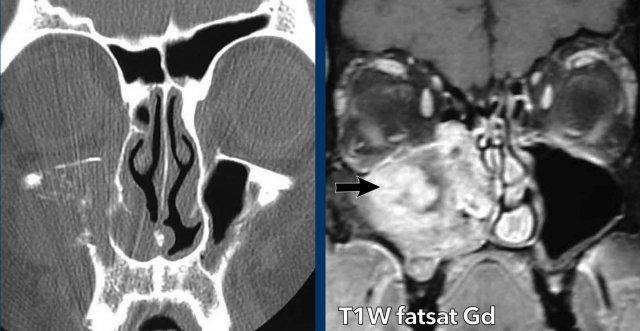

Ung thư biểu mô tế bào vảy

Đây là một ví dụ khác về tổn thương có kiểu tăng trưởng phá hủy.

Lưu ý tình trạng ngấm thuốc tương phản từ của khối u trên MRI (mũi tên).

Có xâm lấn vào hốc mắt (phần trong).

Sinh thiết cho thấy ung thư biểu mô tế bào vảy.